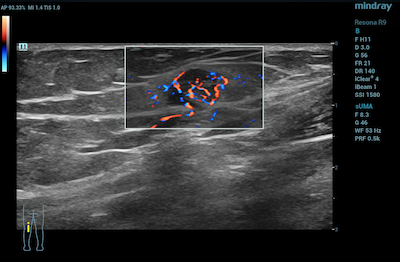

- Reproductive System – CDI is advantageous in evaluating uterine abnormalities, assessing the ovaries and testes for the absence of blood flow in instances of torsion, and even penile Doppler for various male reproductive conditions.

Color Doppler Imaging of Ovarian Perfusion